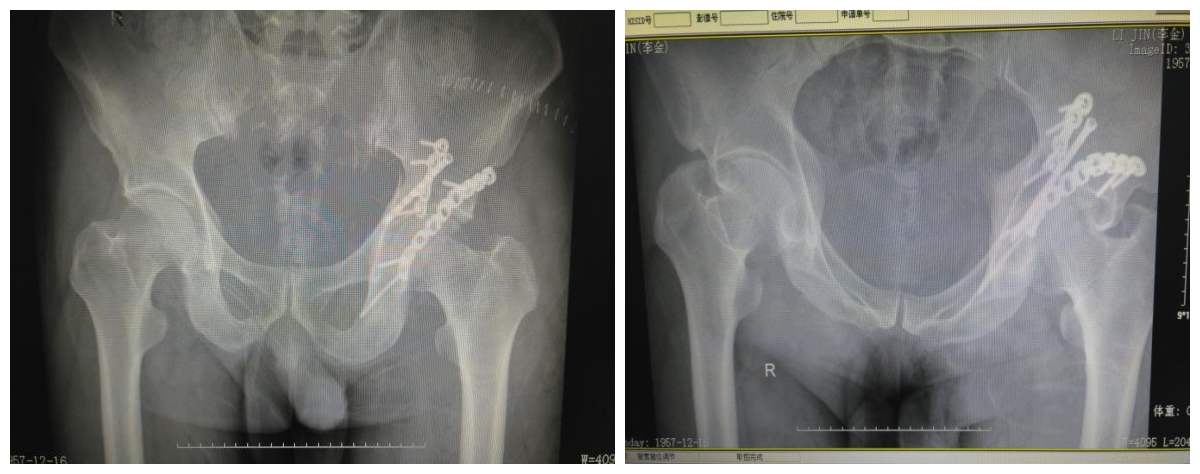

(术后复查DR)